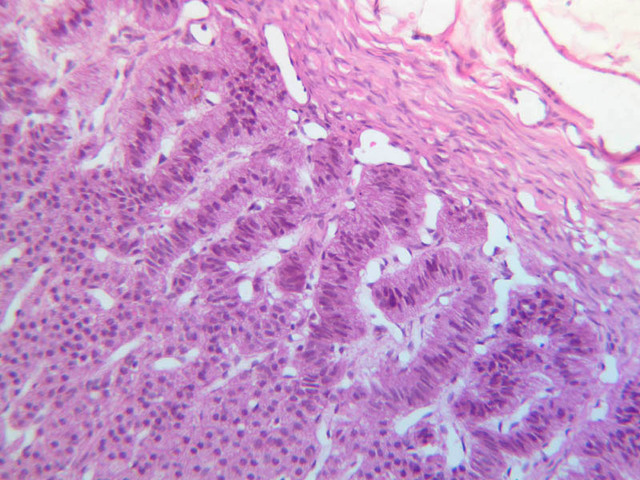

The thyroid gland (slide B-51, lead hematoxylin [10x, 20x, 40x, 40x]; B-52, H&E [10x-labeled, 20x, 40x-labeled, 40x]; B-53, PAS [2.5x, 10x, 20x, 40x]) consists of many closely packed, roughly spherical structures known as follicles, which are enclosed in a thick connective tissue capsule. Connective tissue septa extend from the capsule into the substance of the gland, carrying numerous blood vessels. Follicular cells are arranged as shells of simple cuboidal epithelium surrounding a gelatinous mass known as colloid. Look for a ring of epithelial cells around the homogeneous, pink-staining colloid. The cytoplasm of the follicular cells (principal cells) is faintly basophilic. The follicular cells secrete thyroglobulin, a glycoprotein, which is stored extracellularly in the colloid. In response to TSH, the follicular cells endocytose the colloid and hydrolyze it to form thyroxine. You can see where colloid has been resorbed because this process leaves small holes in the colloid adjacent to the follicular cells. These holes are known as resorption lacunae (B-52 [10x, 20x, 40xlabeled]). Very active follicles may exhibit a columnar epithelium and increased numbers of resorption lacunae. Between follicles, the stroma of the thyroid gland consists of a thin layer of connective tissue and a rich capillary network. Parafollicular cells (light cells or C cells) are located in the connective tissue between follicles or adjacent to follicular cells within follicles. When they lie within the follicular wall, the parafollicular cells do not reach the lumen. Parafollicular cells are slightly larger than the follicular cells and, in H & E preparations, have a more lightly stained cytoplasm (B-52, H&E [10x, 20x, 40x-labeled] [10x-labeled, 20x, 40x-labeled] [10x, 20x, 40x] [10x, 20x, 40x]; B-53, PAS [10x, 20x, 40x]). Parafollicular cells are readily identifiable in slide B-51 (stained with lead hematoxylin), where they appear as purplish-black structures in which the nuclei are difficult to discern (B-51 [10x, 20x, 40x-labeled]). These cells secrete calcitonin, which lowers serum calcium levels by inhibiting bone resorption and accelerating osteoid calcification.